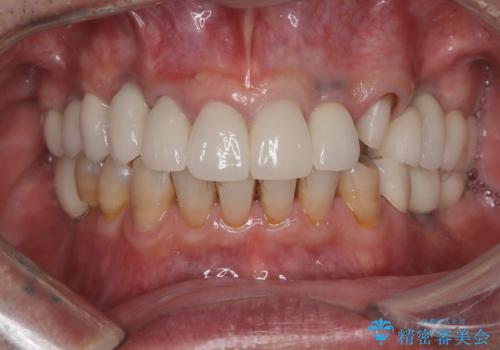

- 「被せ物が揺れている」を主訴に来院された患者様です。診査診断を行い被せ物が外れているのではなく、コアという土台ごと外れていたので、土台ごとやり変えた後オールセラミッククラウンで治療を行いました。

ファイバーコアという土台を建てるときに唾液が入ると接着に良くないのでラバーダムシートを使用しています。加えてマイクロスコープを使用しながら行う事で外れにくい土台を作ることが出来ます。その後、形成を行いシリコンで型取りしたのち、オールセラミッククラウンで修復しました。